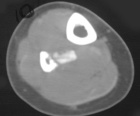

S.P. - 15 year old female presents with two month hx of right calf pain. Pain awakens her from sleep.